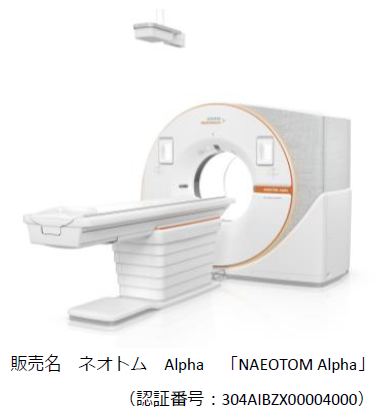

シーメンスヘルスケア株式会社(東京都品川区、代表取締役社長:森 秀顕、以下 シーメンスヘルスケア)は、フォトンカウンティング検出器を搭載した次世代CT「NAEOTOM Alpha(ネオトム アルファ)」が名古屋市立大学病院へ導入されたことをお知らせする。この導入は、国内6台目となり、中部地域へは初となる。

「NAEOTOM Alpha」の導入により、より迅速で安全、精密な診断が必要とされる患者への、良質な医療の提供につながることが期待される。今回導入した名古屋市立大学病院では本製品を使用した診断を既に開始している。

「NAEOTOM Alpha」は、Siemens Healthineers AG(ドイツ・エアランゲン)が、半導体メーカーである株式会社アクロラド(沖縄県うるま市、代表取締役社長:大野良一)と15年にも及ぶ研究開発の末、実用化された。

NAEOTOM Alphaの「フォトンカウンティング検出器を搭載した最新のデュアルソースCT(2つのX線管と検出器を搭載したCT)」といった大きな特徴を活かしたスペクトラルイメージングにより、1秒未満といった短い時間での70cmを超える広範囲の撮影、心臓など動きのある臓器においても高精細な画像の取得が可能となる。息止めが難しい場合や小児など様々な状況にある患者の負担軽減を実現しながら、様々な疾患において早期発見や正確な診断への貢献が期待されている。

(認証番号:304AIBZX00004000)

「NAEOTOM Alpha」について

本製品は、Siemens Healthineersがアクロラドとともに開発した「フォトンカウンティング検出器」を搭載している。主に被ばくを低減しつつ高分解能な画像を臨床利用できるという点で、従来のCT装置から大きなイノベーションを果たした。

フォトンカウンティング検出器は、従来の検出器のようにX線光子を可視光に変換するのではなく、各X線光子とそのエネルギーレベルを直接検出するため、より少ない放射線量で高解像かつ有用なデータを提供することができる。また、被ばくを抑えることができるため、患者や検査を受ける人の負担を減らしつつ正確で包括的な検査が可能となる。その応用範囲は、腫瘍や心臓の診断から肺のフォローアップ検査まで、幅広く多岐にわたる。